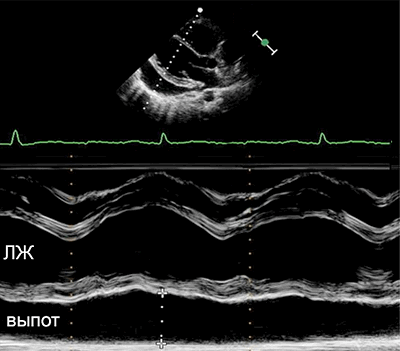

• Эхокардиография: выпот, утолщение перикарда.

• Выпот (>15–35 мл), сепарация эпикарда и перикарда >1 мм в диастолу.

• Величина выпота: малый (сепарация • Утолщение (>3–4 мм) и кальцификация перикарда (констриктивный перикардит).

• Эхокардиография: колебания сердца, выраженный выпот (>20 мм), диастолический коллапс камер сердца, аномальное движение МЖП, > вариабельности митрального потока (>25%) на вдохе.

• Выраженная сепарация эпикарда и перикарда >20 мм в диастолу на эхокардиограмме.

УЗИ сердца при перикардитах

УЗИ при перикардите